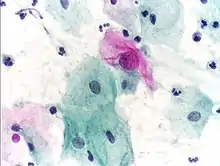

Micrograph of a Pap test showing a low-grade intraepithelial lesion (LSIL) and benign endocervical mucosa. Pap stain.

Pap tests commonly examine epithelial abnormalities, such as metaplasia, dysplasia, or borderline changes, all of which may be indicative of CIN. Nuclei will stain dark blue, squamous cells will stain green and keratinised cells will stain pink/ orange. Koilocytes may be observed where there is some dyskaryosis (of epithelium). The nucleus in koilocytes is typically irregular, indicating possible cause for concern; requiring further confirmatory screens and tests.